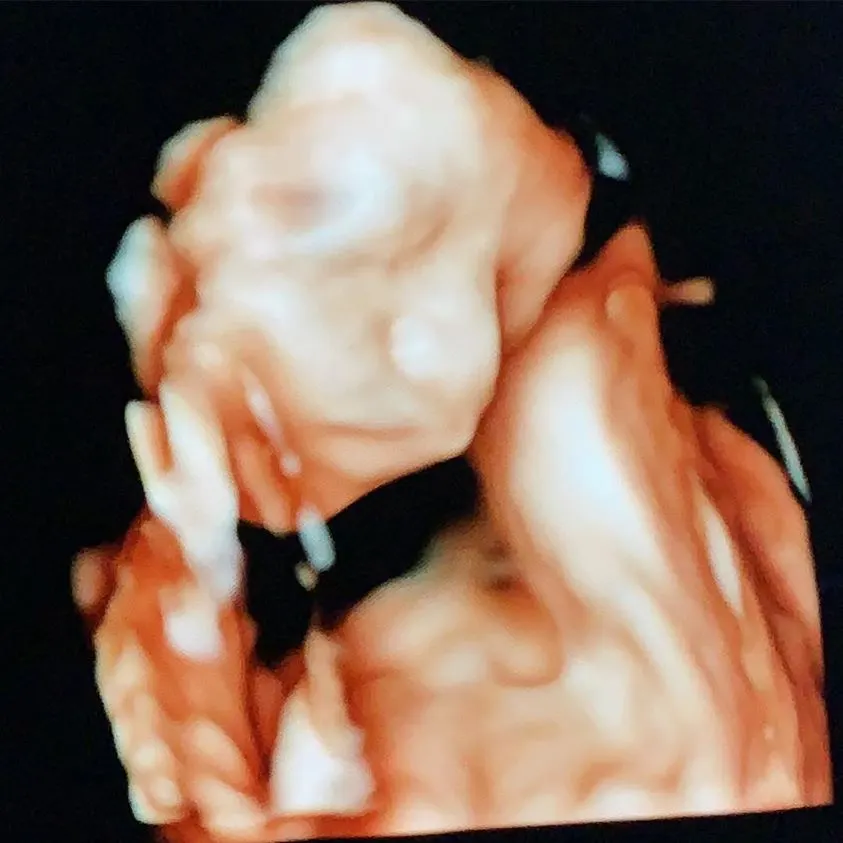

วันนี้ 1 เมษายน 2562 ‘น้องบุญ’ ลูกชาย บุ้ง สะธี หรือ บุ้ง ใบหยก ภรรยาสุดที่รักของ เวฟ-สาริน ได้ลืมตาดูโลกครั้งแรก พร้อมเป็น ทายาทคนใหม่ของตระกูลตึกใบหยก หน้าตาน่ารัก น่าชัง เหมือน พ่อ แม่ ไม่มีผิด ซึ่งทางเรา ก็ขอแสดงความยินดีกับทั้งคู่ด้วย ที่จะได้เป็นพ่อแม่มือใหม่ เป็นพ่อแม่ป้ายแดง